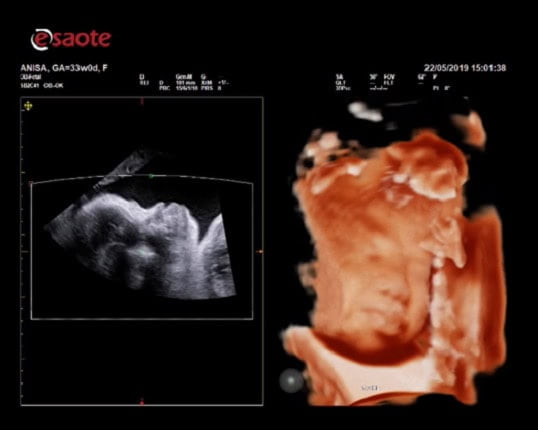

Siêu âm sản phụ khoa

XLight - phần mềm siêu âm sản 3D/4D chuyên sâu cho mặt thai nhi mịn, chân thật. Nhờ công nghệ bố trí nguồn sáng ảo và khả năng tái tạo bề mặt.

may sieu am mylab x7